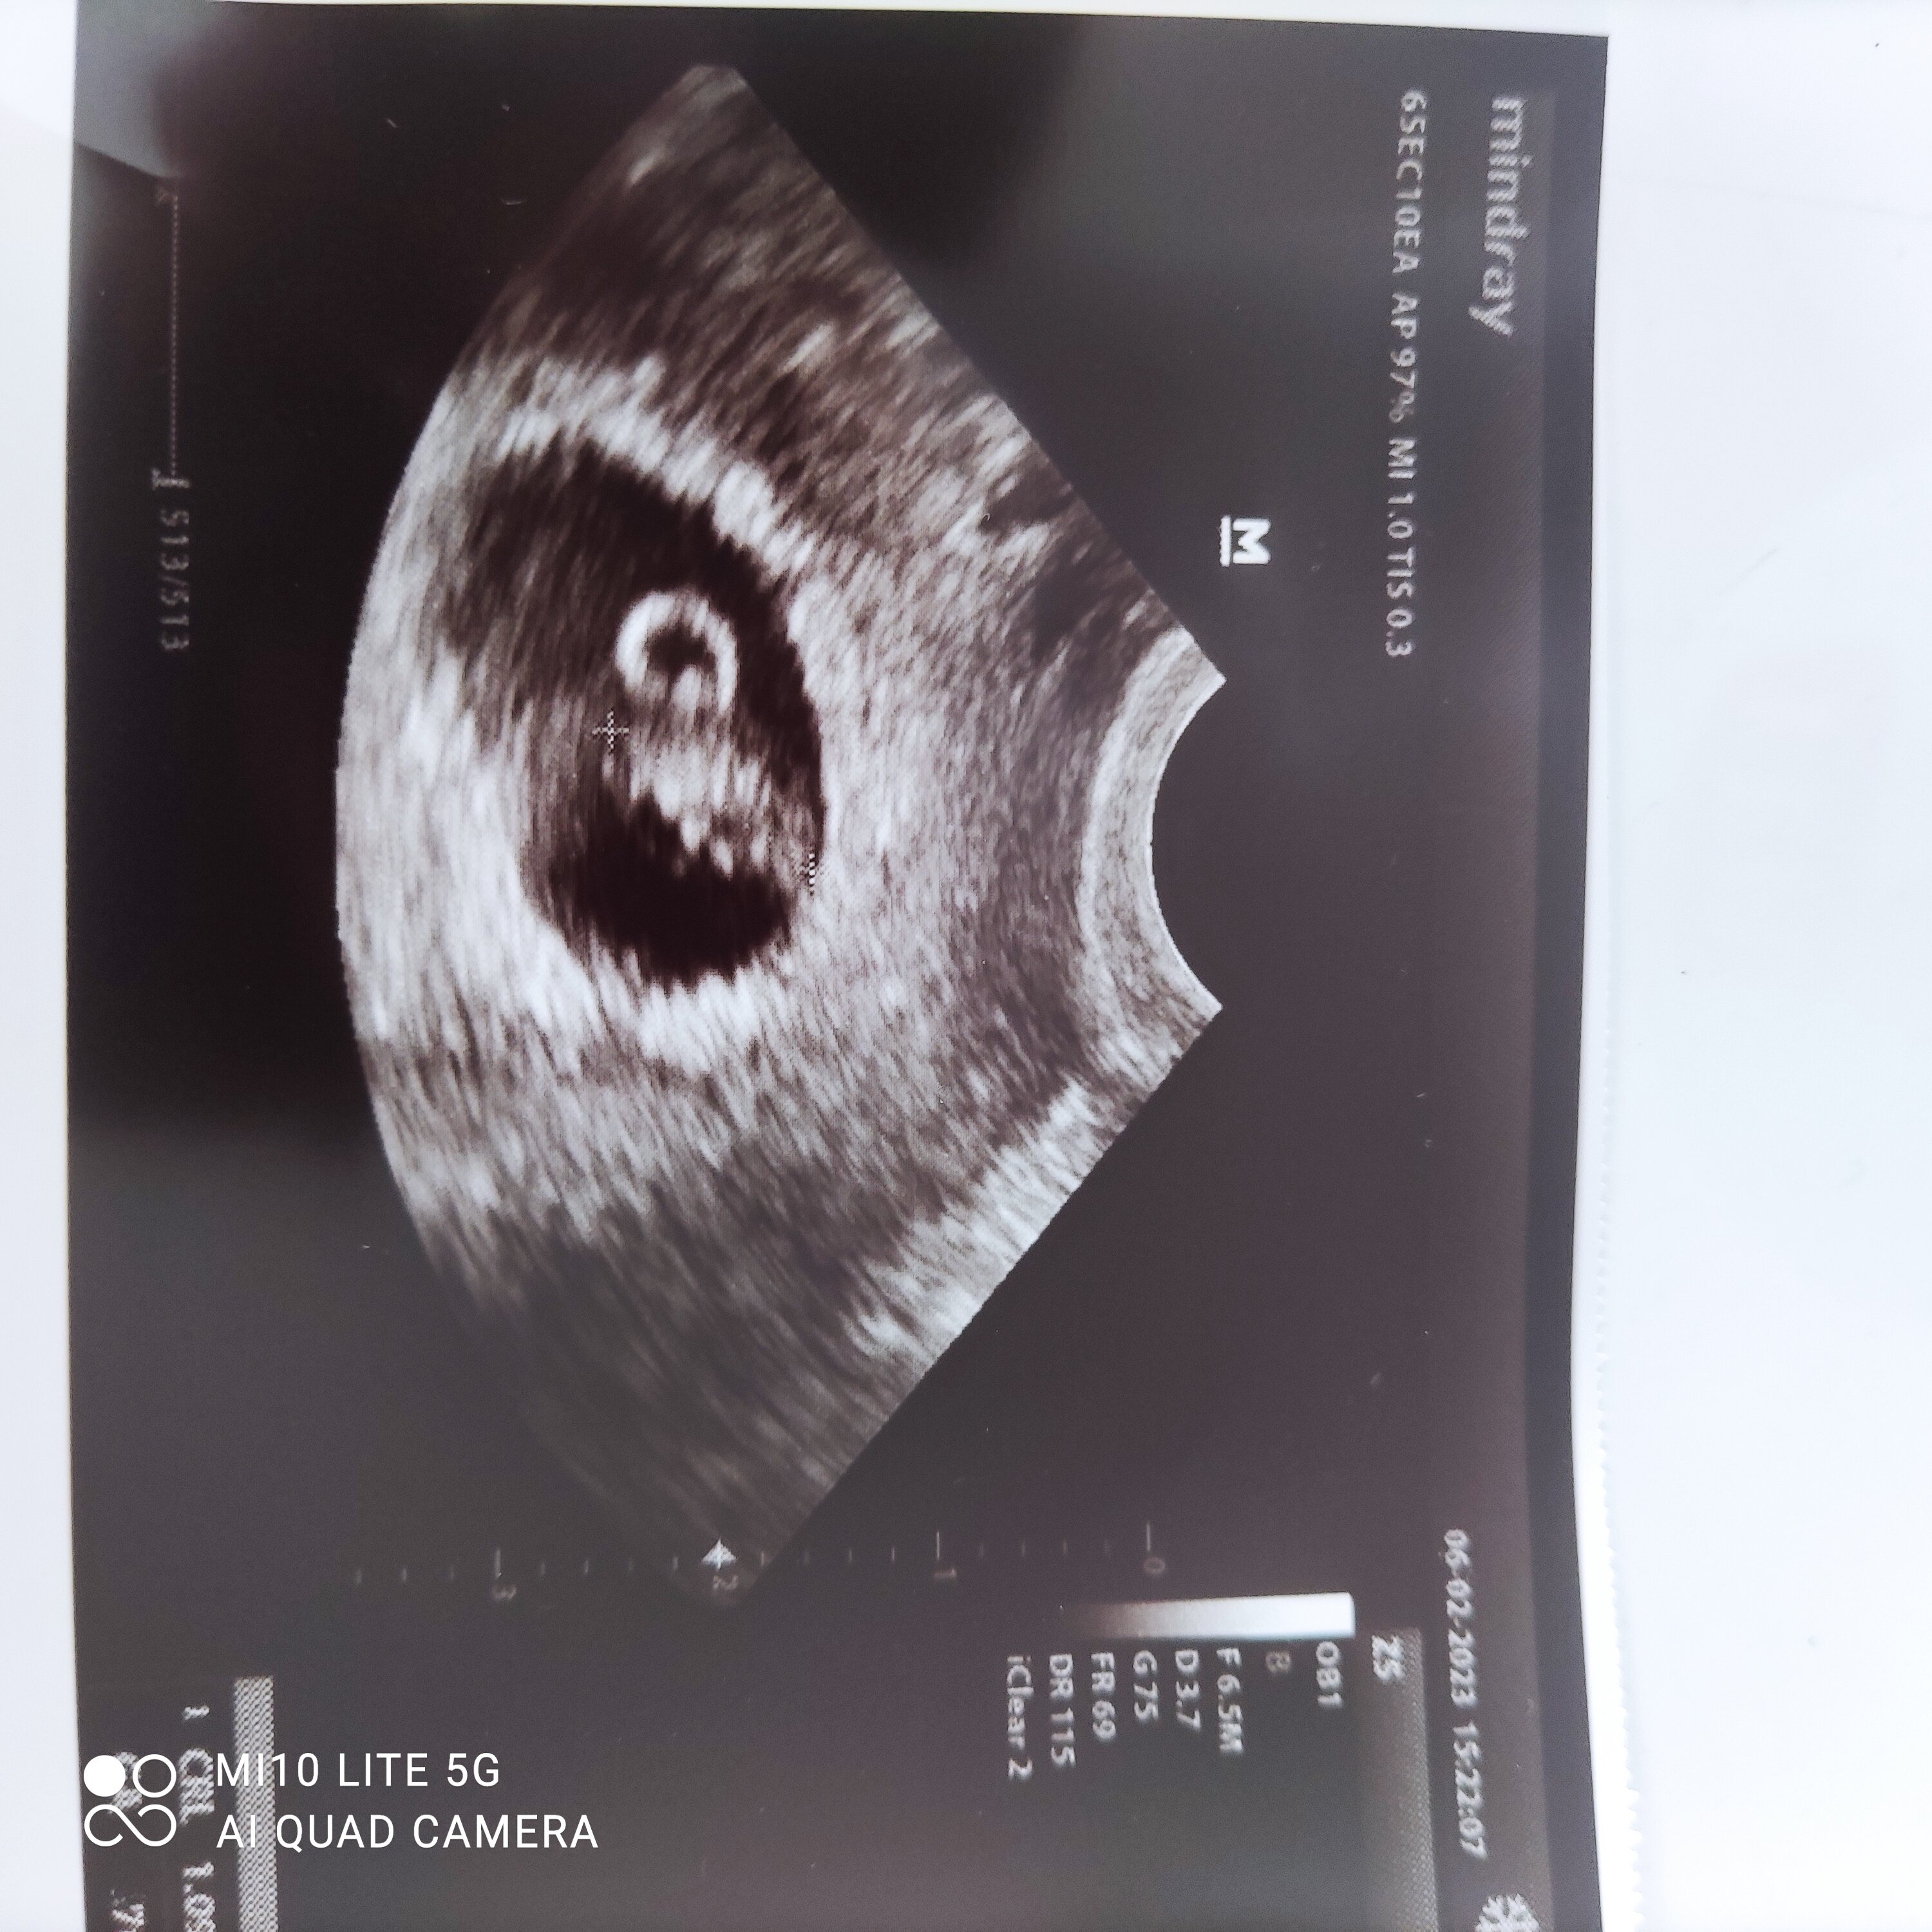

Kochane ja już po wizycie. Jak to mąż stwierdził ,,byk'' -cały 1cm🙈🙈 serducho pulsuje, kolejna wizyta 13.02🥰 dodaję foto a co tam, chociaż tu się pochwalę 😉

Załączniki

• IMG_20230206_091206.jpg

IMG_20230206_091206.jpg

1 MB · Wyświetleń: 105